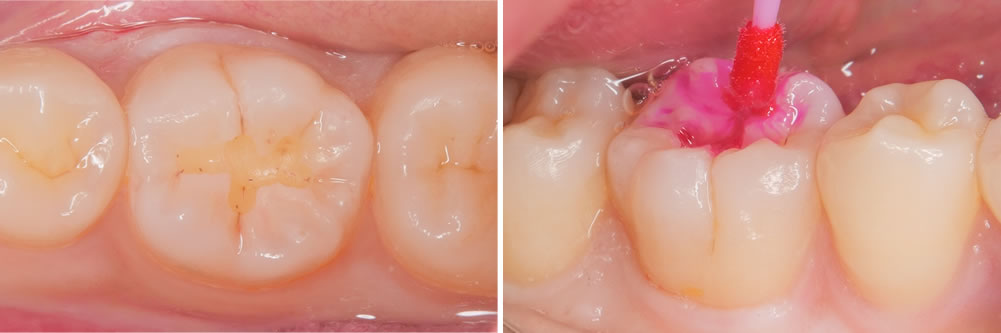

う蝕検知液を用いて丁寧に虫歯を取り除いていきます。

酸処理

内部の虫歯を取り除いた状態です。接着力を上げるため酸処理を行いました。

接着処理

酸処理後には接着処理を行います。

CR充填

コンポジットレジンという樹脂の材料を用いて削った部分を埋めていきます。

形態を整えて歯の形にしていきます。

治療完了

形態修正と研磨を行い、治療が終わりました。